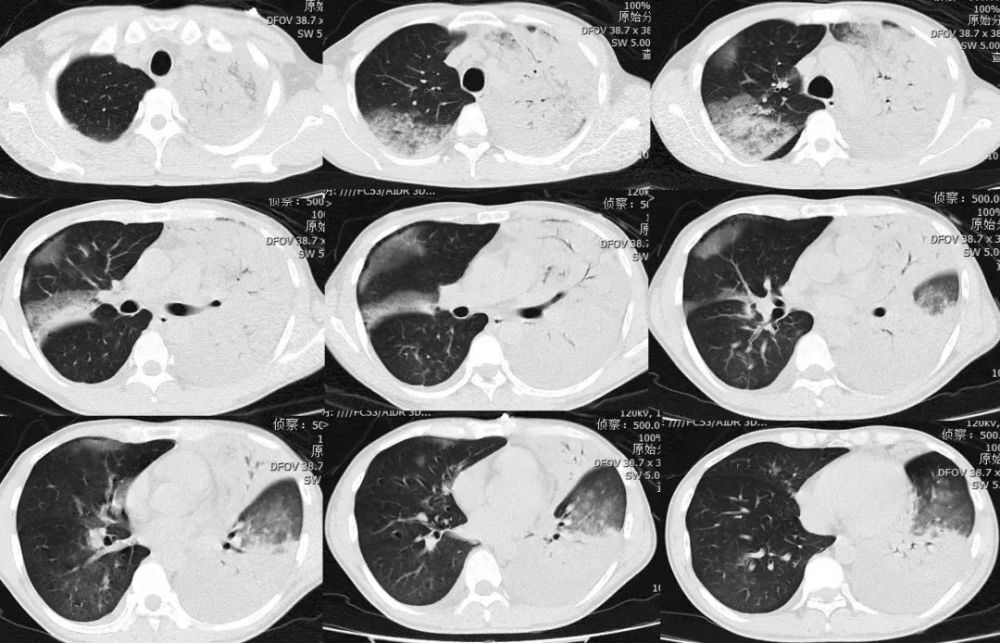

呼吸道合胞病毒肺炎:双肺小叶中心结节灶,支气管管壁增厚f58,急性髓系

小叶性肺炎--支气管炎及支气管周围炎一小簇腺泡为主,支气管壁变厚

在ct上表现有:又称为小叶性肺炎,多见于

2 小叶性肺炎(支气管肺炎) 当病原体侵犯周围呼吸道上皮,引起支乒管

(二)支气管肺炎支气管肺炎又称为小叶性肺炎,常见于婴幼儿和年老体弱